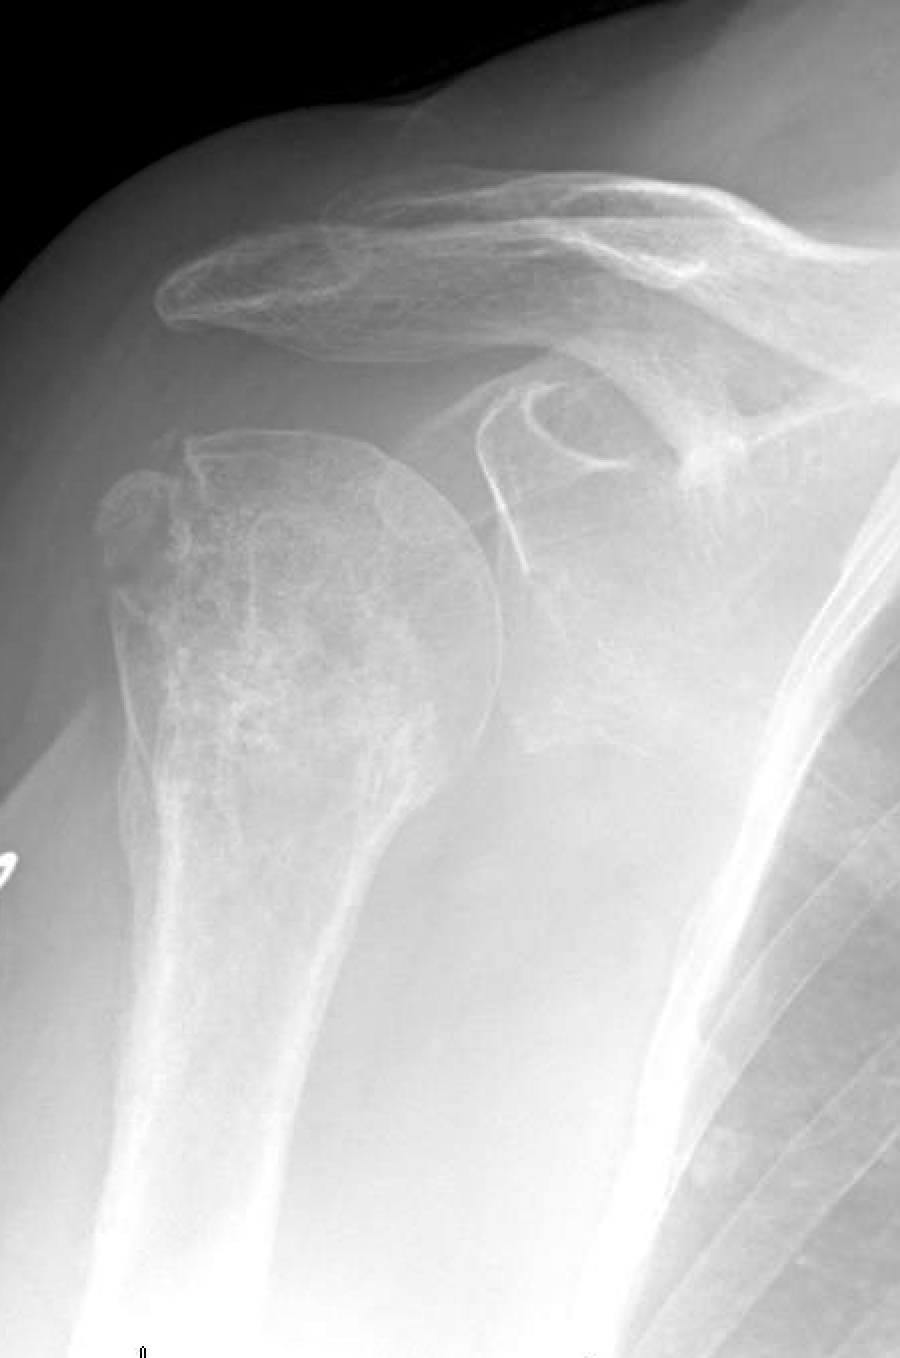

Shoulder and Elbow Surgery Osteoporosis and collapse of the head after ORIF of the proximal

Shoulder and Elbow Surgery Osteoporosis and collapse of the head after ORIF of the proximal Elbow Pain After Humerus Surgery   a distal humerus fracture is a break in the lower end of the upper arm bone (humerus), one of the three bones that come together to form the elbow joint.  a distal humerus fracture is a break in the lower end of the humerus (upper arm bone), one of the three bones that come together. Talk to your. Elbow Pain After Humerus Surgery.